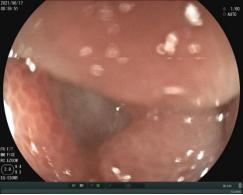

经胃镜检查,其结果发现十二指肠球部溃疡疤痕狭窄,胃镜不能通过十二指肠球部。患者病因找到为十二指肠溃疡疤痕狭窄导致的梗阻。大量胃液丢失可导致血液中氢离子(H+)水平降低,导致代谢性碱中毒,身体为了纠正碱中毒,会把血液中的钾离子泵入细胞,把细胞内的H+交换出来,造成碱中毒——低钾这一恶性循环;同时因大量消化液丢失导致血容量不足,进而导致肾功能不全等渗性脱水、低钾、代谢性碱中毒这一系列的临床表现。

胃镜检查提示十二指肠肠腔狭窄,胃镜不能通过